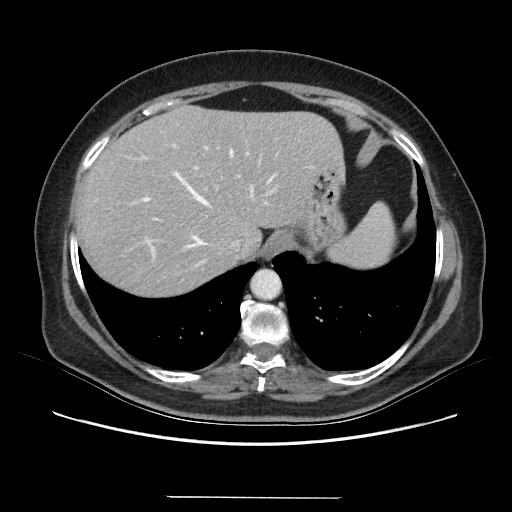

Original VENOUS CT scan

No window - Raw intensity values

Lung window (WL -600, WW 1500 β†’ Low βˆ’1350, High +150)

Mediastinum window (WL 40, WW 400 β†’ Low βˆ’160, High +240)